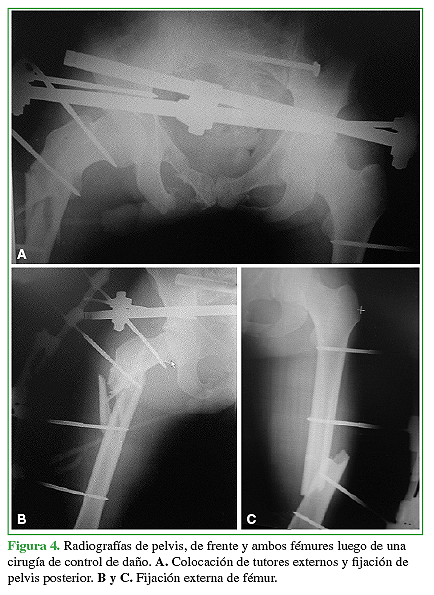

Luego de la revisión primaria y la reanimación inicial según el protocolo ATLS con la estabilización transitoria de la fractura mediante tutores externos, se programó la osteosíntesis (Figuras 3,4y 5).

La fractura de fémur había sido tratada con clavos endomedulares en el 95,7% (n = 22) (Figura 6) y con placa y tornillos solo en el 4,3% (n = 1). La mediana de días de internación de esta población fue de 8 (rango 5-10). La mediana de la duración de los procedimientos fue de 247 min (rango 120-480) y la mediana de la pérdida hemática estimada durante la operación, de 500 ml (rango 300- 900).

La mediana de los procedimientos traumatológicos realizados por paciente fue de 5 (rango 4-5). La mediana del tiempo de espera para la resolución total de la CF fue de 12 días (rango 2-54) principalmente demorado por el estado clínico-hemodinámico del paciente. En el momento del alta, 17 (73,9%) pacientes no tenían dolor y dos (8,8%) presentaban una lesión del nervio ciático poplíteo externo, que remitió por completo en ambos casos, a los seis y ocho meses de la cirugía. El 56,5% (n = 13) sufrió lesiones asociadas (Tabla 2).

Lograr siempre la reducción y estabilización de la fractura de fémur, como primer acto quirúrgico, nos permitió llevar a cabo una mejor preparación del paciente, lograr un mejor posicionamiento en la mesa operatoria en el momento de observar, reducir y estabilizar la fractura de pelvis o acetábulo. Según la bibliografía, el cirujano ortopédico está obligado a examinar la fisiopatología del trauma y evaluar la complejidad de las lesiones de cada paciente traumatizado considerando la necesidad imperiosa de esperar la cirugía definitiva para evitar el segundo impacto inflamatorio que puede producir el acto quirúrgico.14,15